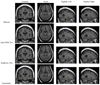

We compared four automated methods for hippocampal segmentation using different machine learning algorithms: 1) hierarchical AdaBoost, 2) support vector machines (SVM) with manual feature selection, 3) hierarchical SVM with automated feature selection (Ada-SVM), and 4) a publicly available brain segmentation package (FreeSurfer). We trained our approaches using T1-weighted brain MRIs from 30 subjects [10 normal elderly, 10 mild cognitive impairment (MCI), and 10 Alzheimer's disease (AD)], and tested on an independent set of 40 subjects (20 normal, 20 AD). Manually segmented gold standard hippocampal tracings were available for all subjects (training and testing). We assessed each approach's accuracy relative to manual segmentations, and its power to map AD effects. We then converted the segmentations into parametric surfaces to map disease effects on anatomy. After surface reconstruction, we computed significance maps, and overall corrected p-values, for the 3-D profile of shape differences between AD and normal subjects. Our AdaBoost and Ada-SVM segmentations compared favorably with the manual segmentations and detected disease effects as well as FreeSurfer on the data tested. Cumulative p-value plots, in conjunction with the false discovery rate method, were used to examine the power of each method to detect correlations with diagnosis and cognitive scores. We also evaluated how segmentation accuracy depended on the size of the training set, providing practical information for future users of this technique.